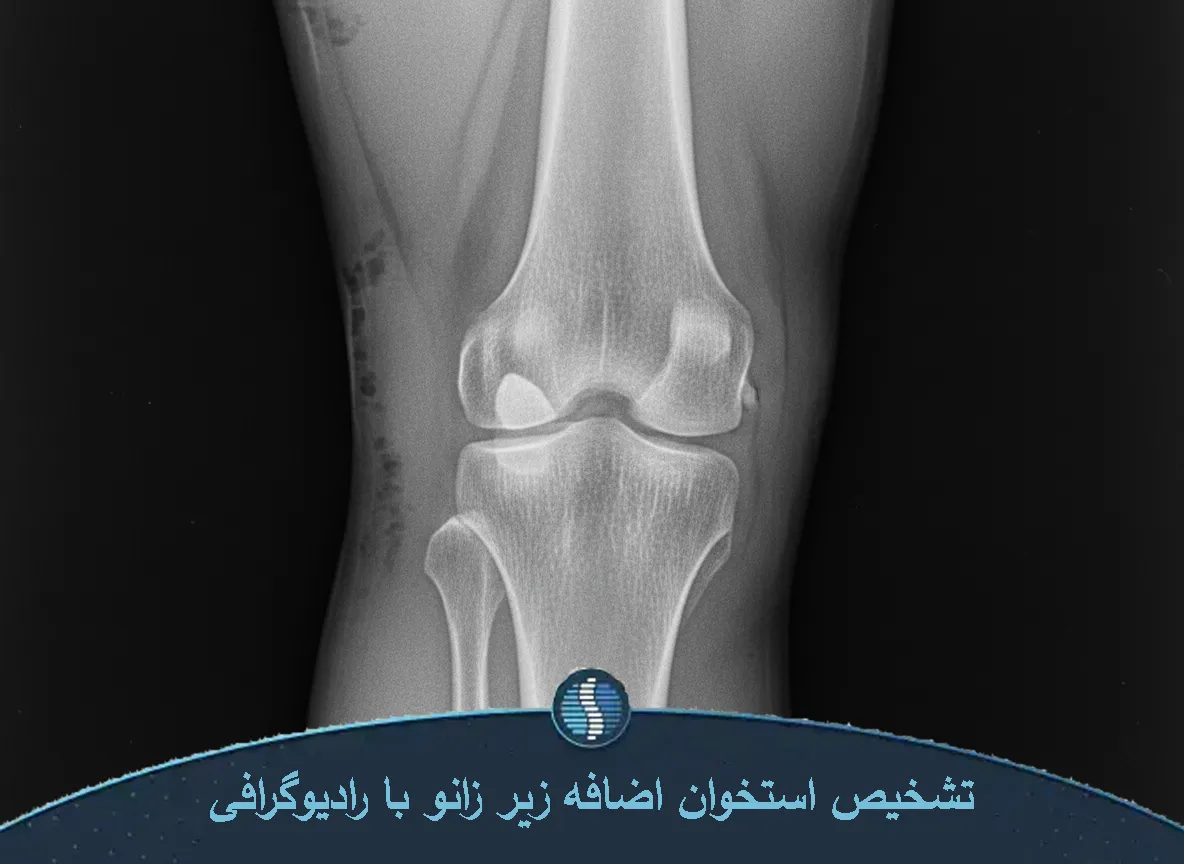

تشخیص این عارضه بر اساس ترکیبی از معاینه فیزیکی و روشهای تصویربرداری مانند رادیوگرافی (X-ray)، سونوگرافی و در موارد پیچیده MRI انجام میشود. هدف تشخیص، تعیین نوع زائده، محل دقیق آن و افتراق بین استئوفیت، رسوب کلسیم و استخوانیشدن تاندون است.

- رادیوگرافی ساده (X-ray)

- رادیوگرافی اولین قدم برای تأیید وجود زائده استخوانی است. عکس ساده زانو بهوضوح اندازه زائده، محل دقیق رشد استخوان و وجود آرتروز یا تغییرات سطح مفصل را نشان میدهد.